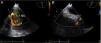

Two years later, a redo routine echocardiographic evaluation revealed the presence of a new small spherical non-mobile right atrial mass (26×26 mm). Its echocardiographic appearance was soft, smooth, and homogeneous. It was located in a small recess near the inferior vena cava opening. Impaired venous return was suspected due to the absence of inferior vena cava respiratory variation, and flow acceleration at the confluence with the right atrium (Figure 1). Transesophageal echocardiography confirmed these findings and ruled out the presence of other tumor foci. Both the mass and the residual atrial septum were shown by Doppler imaging to be richly vascularized (Figure 2).

Transthoracic echocardiography study showing a right atrial mass located near the inferior vena cava opening (A and B – non-conventional views, C – apical 4-chamber view, D – subcostal view) and flow acceleration at the confluence with the right atrium (B). *: right atrial mass; IVC: inferior vena cava; LA: left atrium; LV: left ventricle; RA: right atrium; RV: right ventricle.